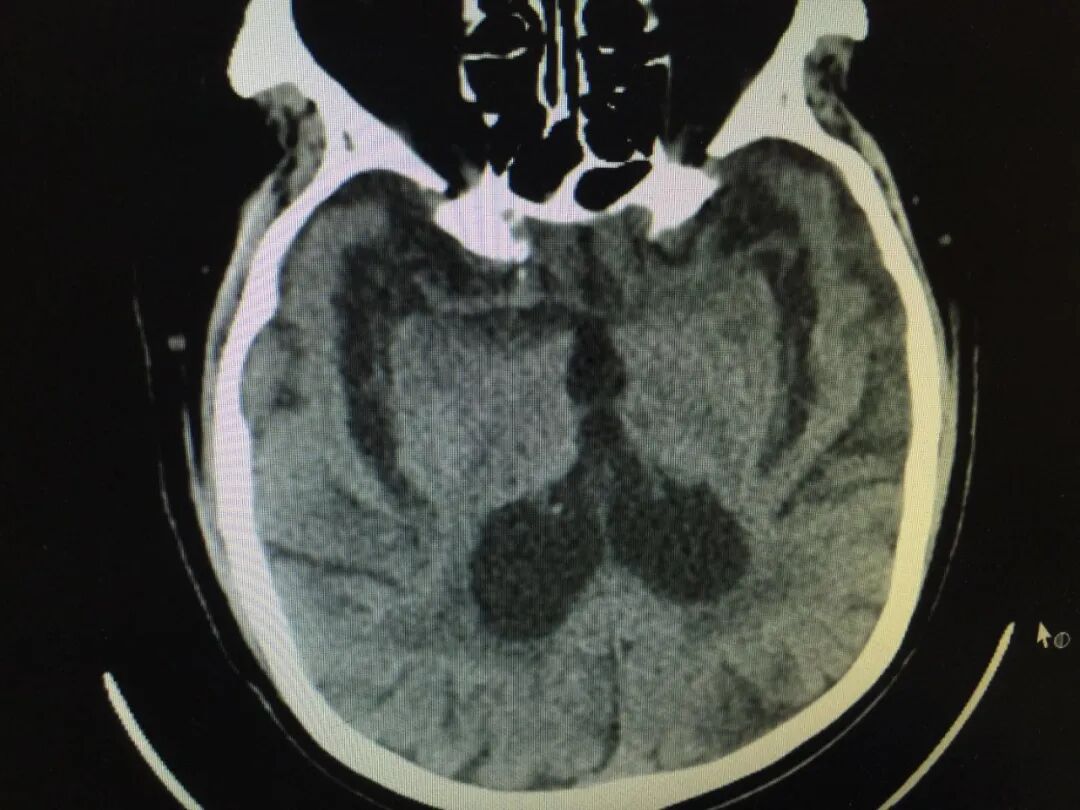

脑萎缩是指由各种原因导致的脑组织本身发生器质性病变而产生萎缩的一种现象。脑萎缩的发病原因多种多样,发病原因除了遗传这一不可避免的影响之外,最常见的致病因素是脑血管长期慢性缺血,导致脑组织处于慢性缺血缺氧状态,脑细胞功能受影响,进而形成脑萎缩。

脑萎缩的常见临床症状最为常见的就是记忆力减退,比如经常丢失日常用品,对近期发生的事件记忆缺损等,其他常见症状有失眠、反应迟钝、性格改变,严重的可能会出现“痴呆”表现。